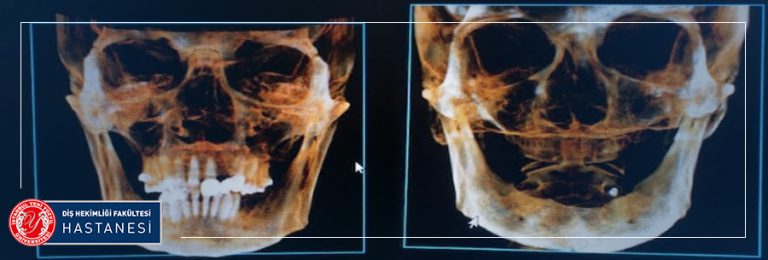

Hastaların fakülteye ilk başvurularında muayenelerinin yapıldığı bölüm Ağız Diş ve Çene Radyolojisi bölümüdür. Ağız, Diş ve Çene Radyolojisi’ne bağlı Oral Diagnoz bölümümüzde; tüm dişler ve ağız içi dokular değerlendirilir. Henüz şikayet olmayan dişlerle ilgili müdahaleler gerekiyorsa, bilgilendirme yapılmaktadır. Hastalıkların teşhis ve tedavilerinde genellikle görüntülenmesi de gerekli olmakta ve bu görüntüleme yöntemleri ve ayrıca diğer kliniklerin ihtiyacı olan radyografi ihtiyaçları da Radyoloji kliniğimizde karşılanmaktadır. Çekilen radyograflar; Gözle yapılan muayenede farkedilmeyen çürük alanlarının, Dolgu altında gelişen yeni çürüklerin, Hijyenik olmayan restorasyonların araştırılmasında, Dişeti hastalıklarında kemik kaybının derecesinin belirlenmesinde, Kanal tedavilerinin başında ve sürecinde, İmplant uygulamalarında kemiğin araştırılmasında, Ortodontik tedavilerin başında ve sürecinde, Çocuklarda diş gelişim ve büyümesinin izlenmesinde, Kemik dokuda ki kist, tümör gibi patolojilerin belirlenmesinde yardımcıdır. Gerekli görüldüğünde ileri görüntüleme ve tetkikler için Tıp hekimliği branşlarından faydalanılmaktadır. Bu bilgilerin ışığında bireye özgü tedavi planı hazırlanmakta ve bu tedavilerin yapılacağı uzman kliniklere hastalar yönlendirilmektedir